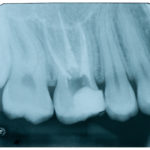

Tomografia computerizzata cone beam in Endodonzia

Accuratezza della tomografia computerizzata cone beam e delle radiografie endorali nella rilevazione di piccole lesioni periapicali.

Accuracy of cone beam computed tomography and periapical radiography in detecting small...